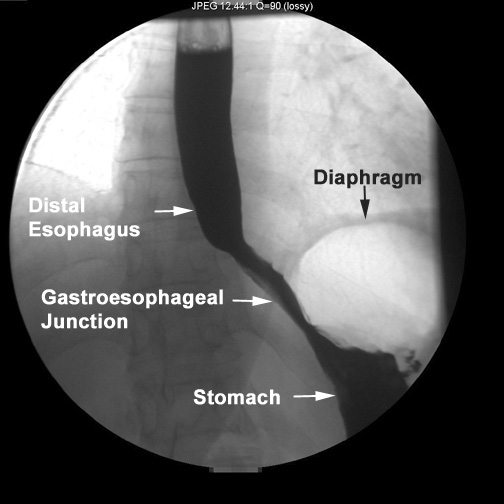

The

cardia is the intersection of the stomach and esophagus.

A ring of muscle known as the cardiac

sphincter is present here